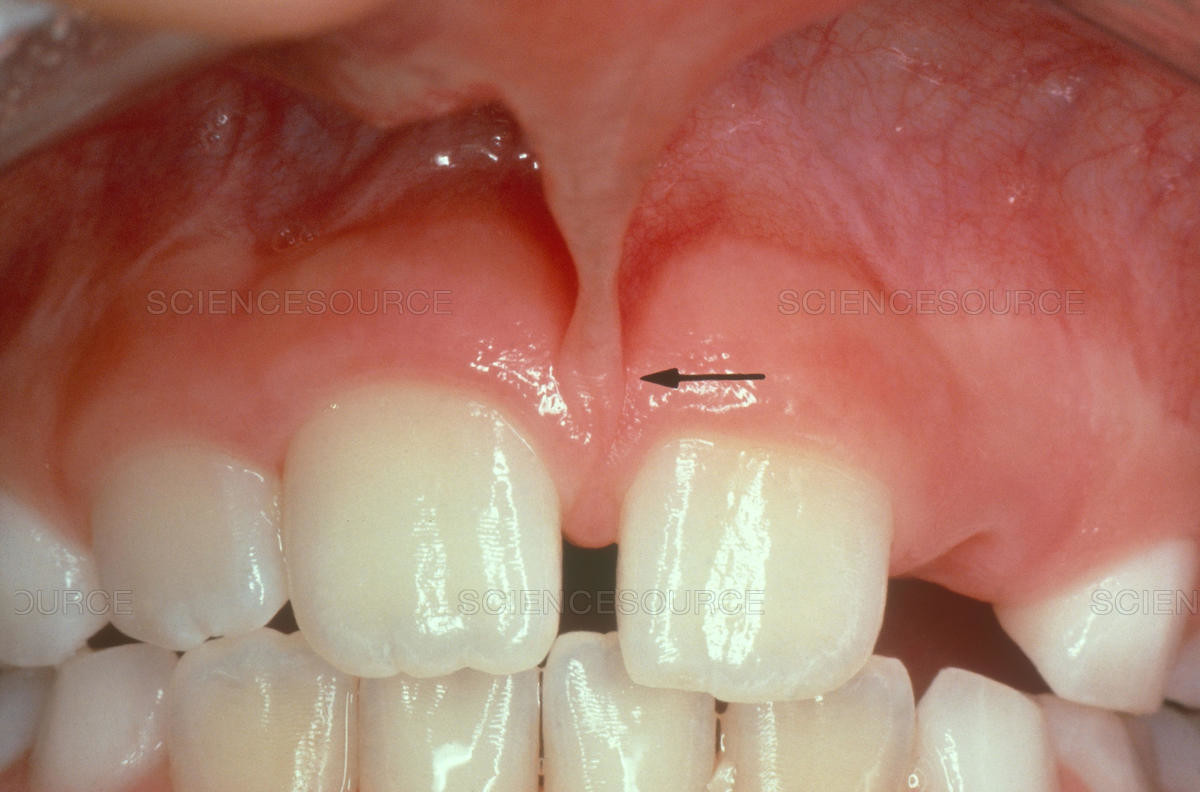

Do Wisdom teeth affect braces?

For those people who have wisdom teeth, they usually erupt in early adulthood. Wisdom teeth may cause dental issues like overcrowding, especially if they’re impacted. However, many people have plenty of room for their wisdom teeth and they have no problems with them.

Like previously stated, many people have their wisdom teeth come in with no problems. The teeth grow in straight and don’t affect the person’s bite. So overall, no, wisdom teeth do not cause significant overcrowding in the front of the mouth or severely disrupt any progress that was made with dental work like braces.

However, if they do not come in correctly or if a person’s jaw simply doesn’t have room for the new teeth, they can cause overcrowding among the back teeth.

While wisdom teeth may not necessarily cause a major issue with the dental progress that has been made with braces, there may still be reasons to have a wisdom tooth extraction. There are many wisdom tooth concerns that may call for tooth removal surgery, including: Crowding of back teeth, Infected gums, Bone defects, Root resorption, Dental diseases.

If a wisdom tooth becomes impacted or doesn’t erupt straight up, this can cause significant problems for the person. While some people may experience absolutely no problems with their wisdom teeth or get lucky enough to not have any of these extra molars at all, others may experience problems with them.

Fortunately, impacted tooth removal is a common procedure and can provide relief from any pain and discomfort caused by these teeth. In fact, wisdom teeth removal is more common than dental implant procedures, which about three million people have every year.

It’s important to remember that it’s perfectly normal for your teeth to move as you age. If your wisdom teeth are beginning to come in and are causing you pain and discomfort, your dentist may refer you to an experienced oral surgeon to discuss having them removed.